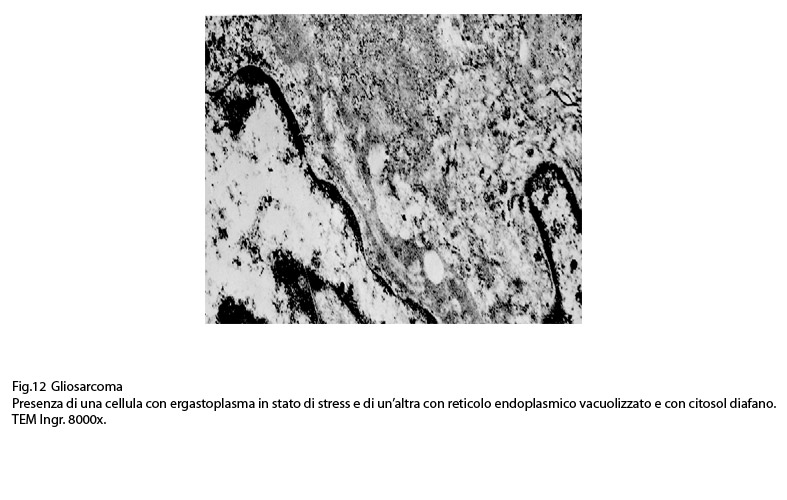

Fig.11  Fig.12

Fig.12